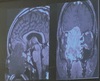

Método de imagen utilizado y dx

A

Difusión, hemorragia de la acm